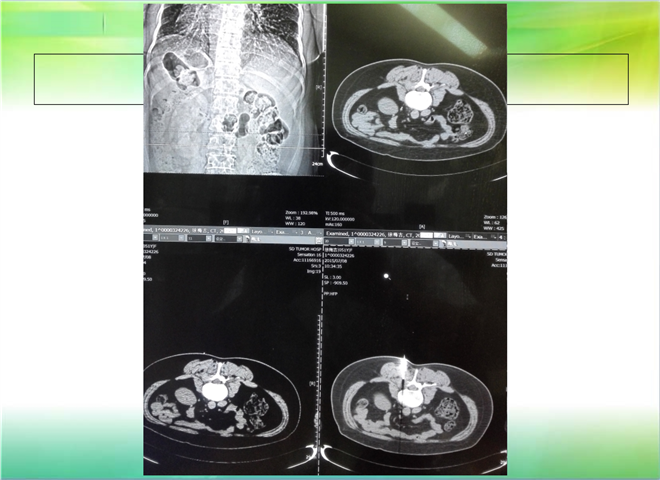

CT引导下穿刺活检术